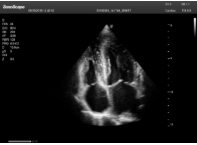

肥厚性心肌病-心尖四腔